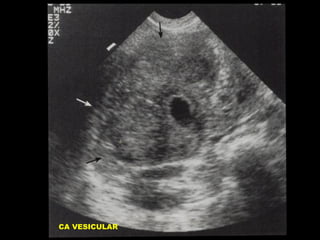

CA VESICULAR

CARCINOMA VESICULAR

Masa Intraluminal